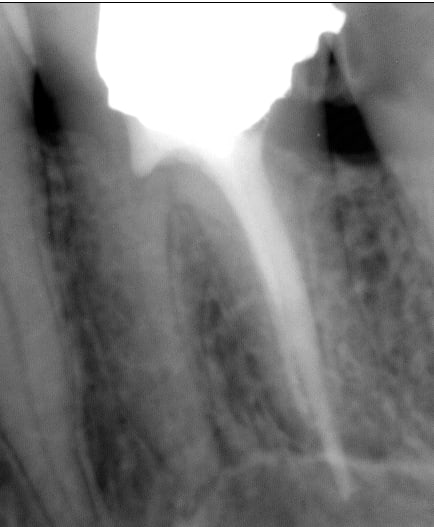

Tu obtures à quoi pour avoir autant de puffs? Par contre ça a l’air efficace sur les canaux accessoires.

youn

27/02/2014 à 18h21

Zizine Zial pour le ciment. pas de desmodontites (très très rares). Les canaux accessoires c'est l'EDTA qu'il faut remercier, et au Mac Spadden je reste un bon moment (5-6 secondes) à 3 mm de l'apex à 30000 tours, et parfois en plus je condense verticalement jusqu'à 4-5 mm de l'apex et je remets un coup de Mac Spadden.

--

www.dentaltradegroup.com